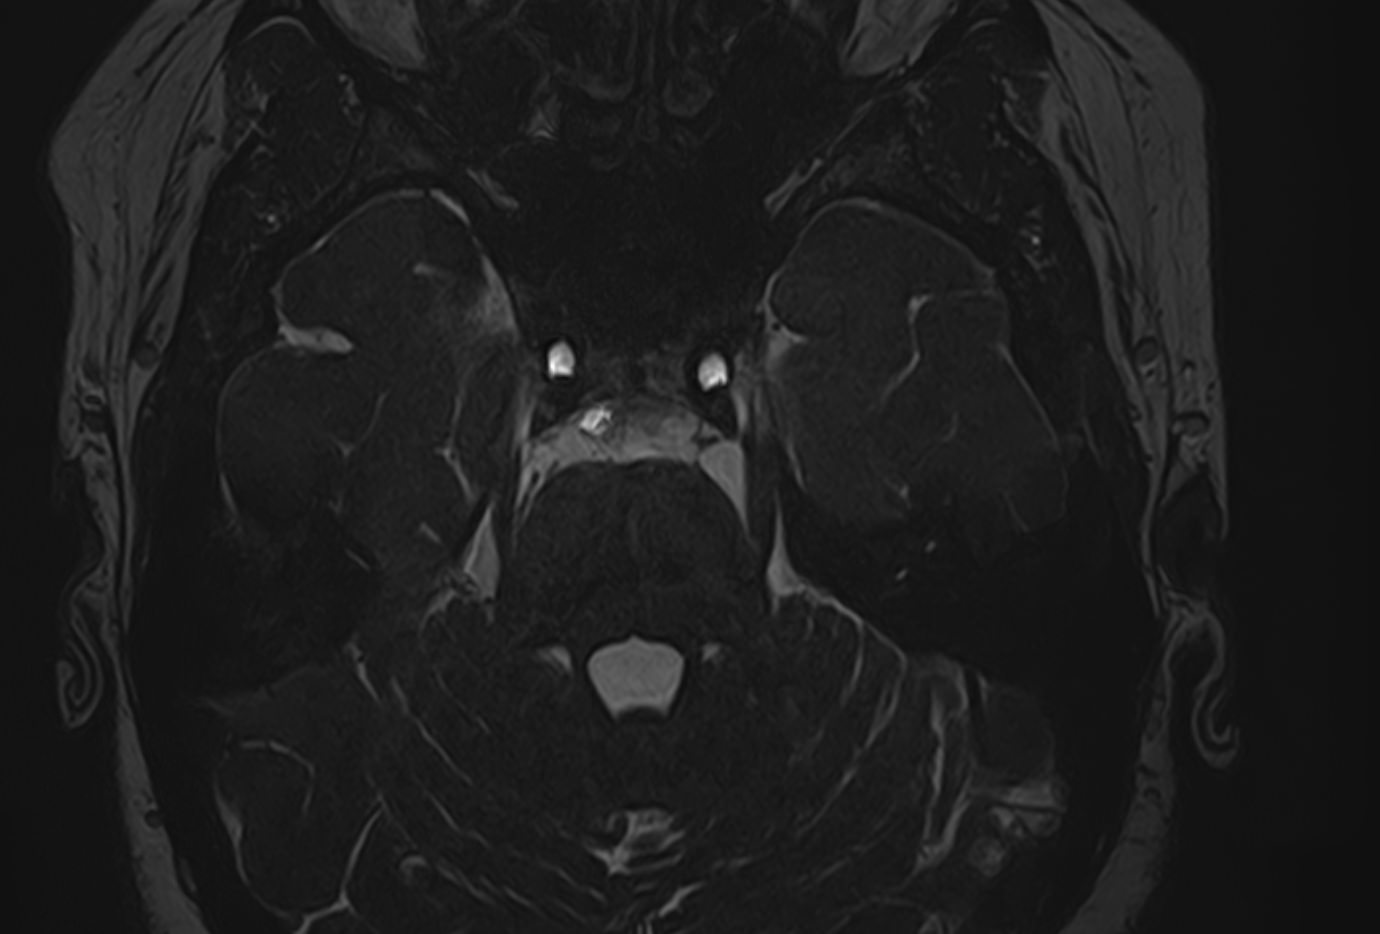

Исследования выполняются на современном высокопольном томографе экспертного класса TOSHIBA VANTAGE TITAN 1,5 Тесла, который использует разные режимы сканирования с толщиной среза от 1мм в различных плоскостях с последующей цифровой обработкой полученных данных для создания трехмерных изображений. МР-ангиография отображает состояние артериальной системы кровоснабжения головного мозга. МР-венография головного мозга позволяет детально изучить особенности венозного русла головного мозга.

Данное комплексное исследование в большинстве случаев проводится с контрастным усилением, которое необходимо для улучшения визуализации черепно-мозговых нервов. Для этого внутривенно вводится препарат, содержащий гадодиамид (соли металла гадолиния) для получения изображений с высокой четкостью и контрастностью, что способствует ранней диагностике заболеваний головного мозга.

• патология нервов на фоне сосудистых проблем (вазоневральный конфликт — сдавление нерва близлежащим сосудом, также на фоне патологической извитости, аневризмы, сосудистой мальформации).